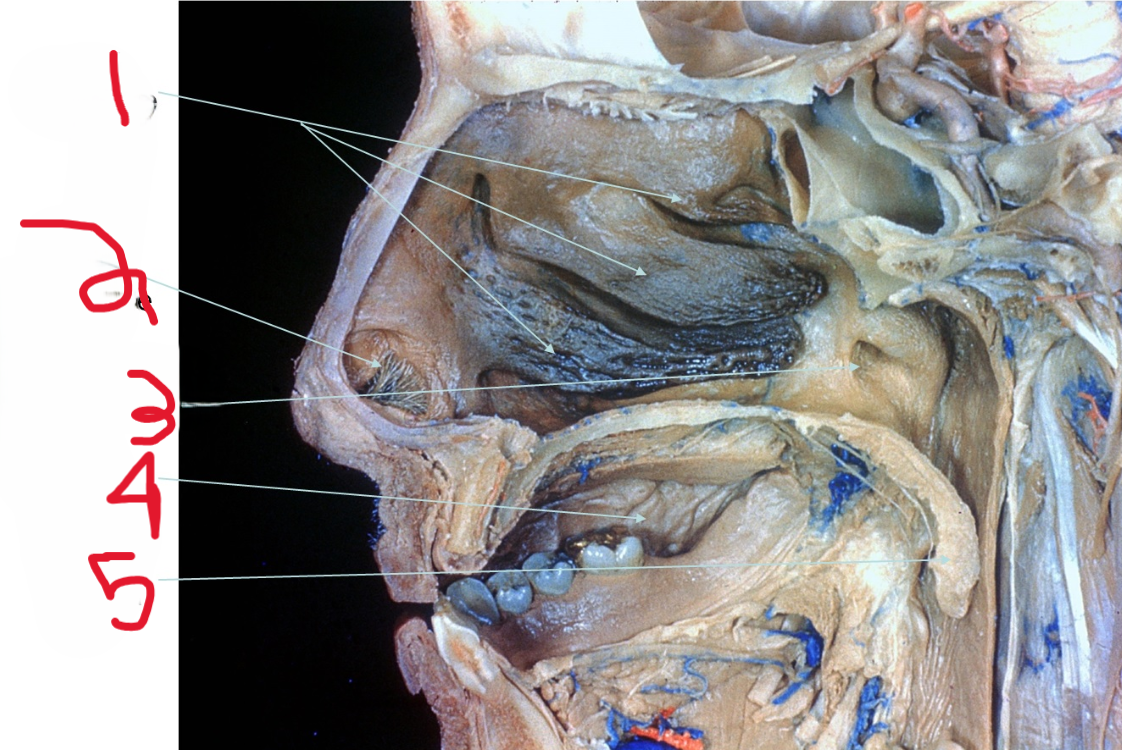

Nasal Conchae

What is depicted by #1

Nasal vestibule

What is depicted by #2

Opening of Pharyngotympanic (auditory) tube

What is depicted by #3

Oral cavity

What is depicted by #4

Uvala

What is depicted by #5